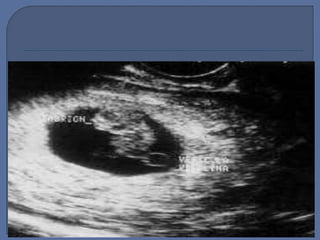

 El embrión es visible a la 6ta semana y la

edad gestacional puede ser valorada a

través de la medición directa de la

longitud cefalo-caudal.

Durante la 7ma semana, el embrión aparece

y la actividad cardiaca se hace visible.

El embrión es visto inicialmente como una

pequeña “mancha” en un borde del saco

vitelino y crece rápidamente.

Una proporción de 1 mm por día.